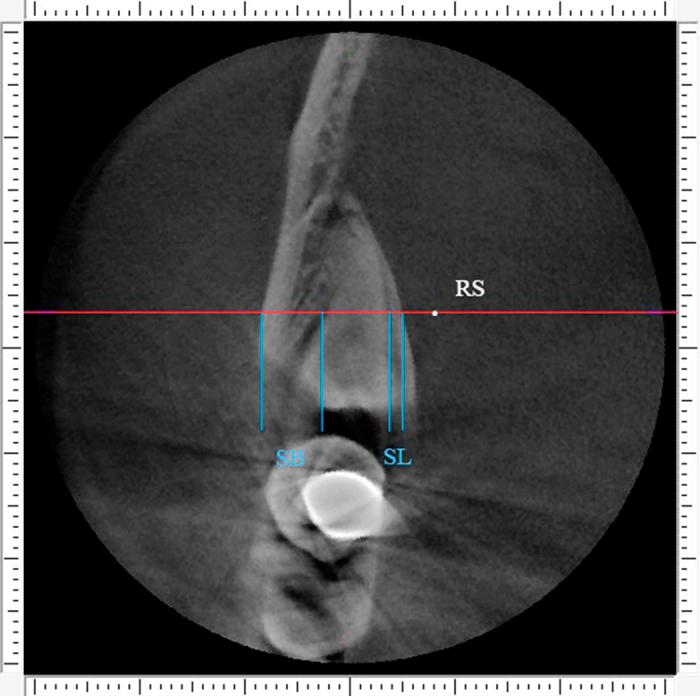

Selecting either buccal or lingual approach for the mandibular third molar surgical extraction has been an intense debate for years. The aim of this observational retrospective study was to classify the molar based on the proximity to the external cortical bone, and analyze the position of inferior alveolar canal (IAC) of each type. Cone-beam CT (CBCT) data of 110 deeply impacted mandibular third molars from 91 consecutive patients were analyzed. A new classification based on the mean deduction value (MD) of buccal-lingual alveolar bone thickness was proposed: MD≥1 mm was classified as buccal position, 1 mm>MD>-1 mm was classified as central position, MD≤-1 mm was classified as lingual position. The study samples were distributed as: buccal position (1.8%) in 2 subjects, central position (10.9%) in 12 and lingual position (87.3%) in 96. Ninety-six molars (87.3%) contacted the IAC. The buccal and inferior IAC course were the most common types in impacted third molar, especially in lingually positioned ones. Our study suggested that amongst deeply impacted mandibular third molars, lingual position occupies the largest proportion, followed by the central, and then the buccal type.

多年来,对于下颌第三磨牙手术拔除选择颊侧或舌侧入路一直存在激烈争论。这项观察性回顾性研究的目的是根据下颌第三磨牙与外侧皮质骨的接近程度对其进行分类,并分析每种类型下颌管(IAC)的位置。分析了91例连续患者的110颗深度埋伏下颌第三磨牙的锥形束CT(CBCT)数据。提出了一种基于颊舌侧牙槽骨厚度平均差值(MD)的新分类方法:MD≥1mm分类为颊侧位置,1mm>MD>-1mm分类为中央位置,MD≤-1mm分类为舌侧位置。研究样本分布如下:2例患者的颊侧位置(1.8%),12例患者的中央位置(10.9%),96例患者的舌侧位置(87.3%)。96颗磨牙(87.3%)与下颌管接触。颊侧和下颌管在下颌管走行是埋伏第三磨牙中最常见的类型,尤其是舌侧位置的。我们的研究表明,在深度埋伏下颌第三磨牙中,舌侧位置占比最大,其次是中央位置,然后是颊侧类型。